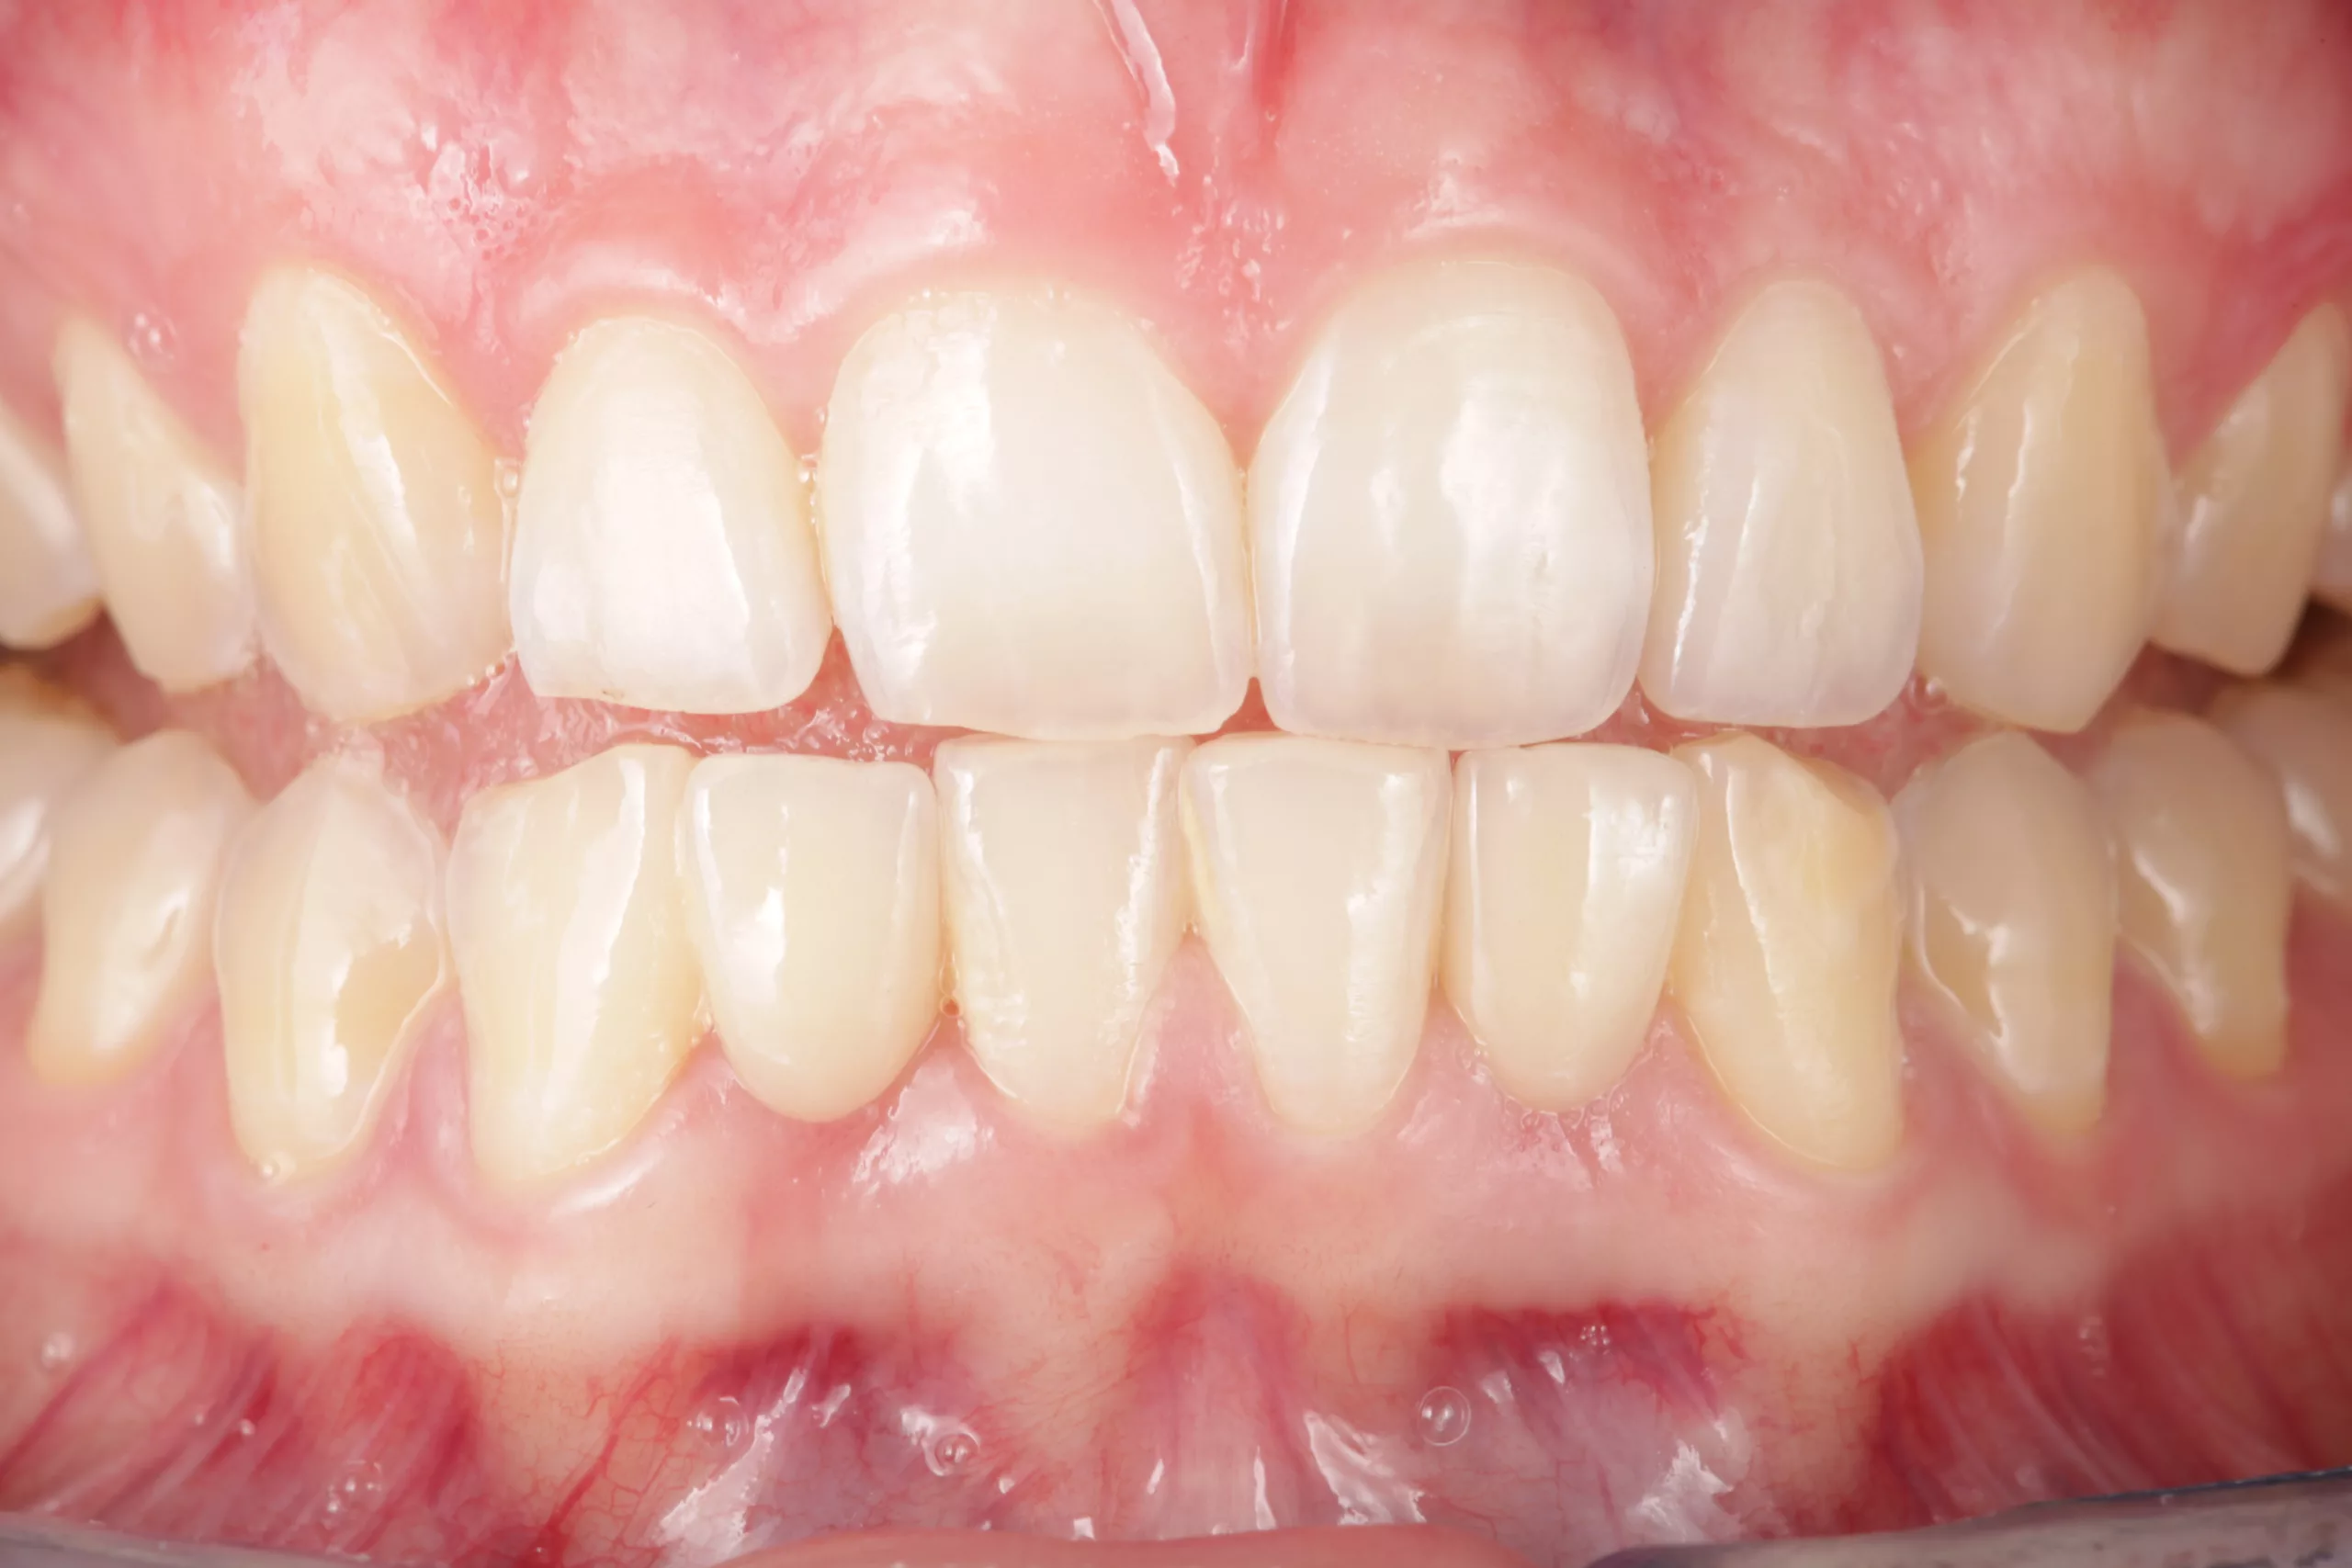

Okklusion und Artikulation können nun überprüft und ggf. angepasst werden. Abschließend folgt die Instruktion des Patienten zur effizienten Reinigung im Bereich der Adhäsivbrücke. Eine Situationsabformung mit anschließendem Situationsmodell und die fotografische Dokumentation des klinischen Ergebnisses helfen bei den Nachsorgesitzungen zur Kontrolle etwaiger Veränderungen der Pfeilerzahnstellung (Abb. 13- 15).